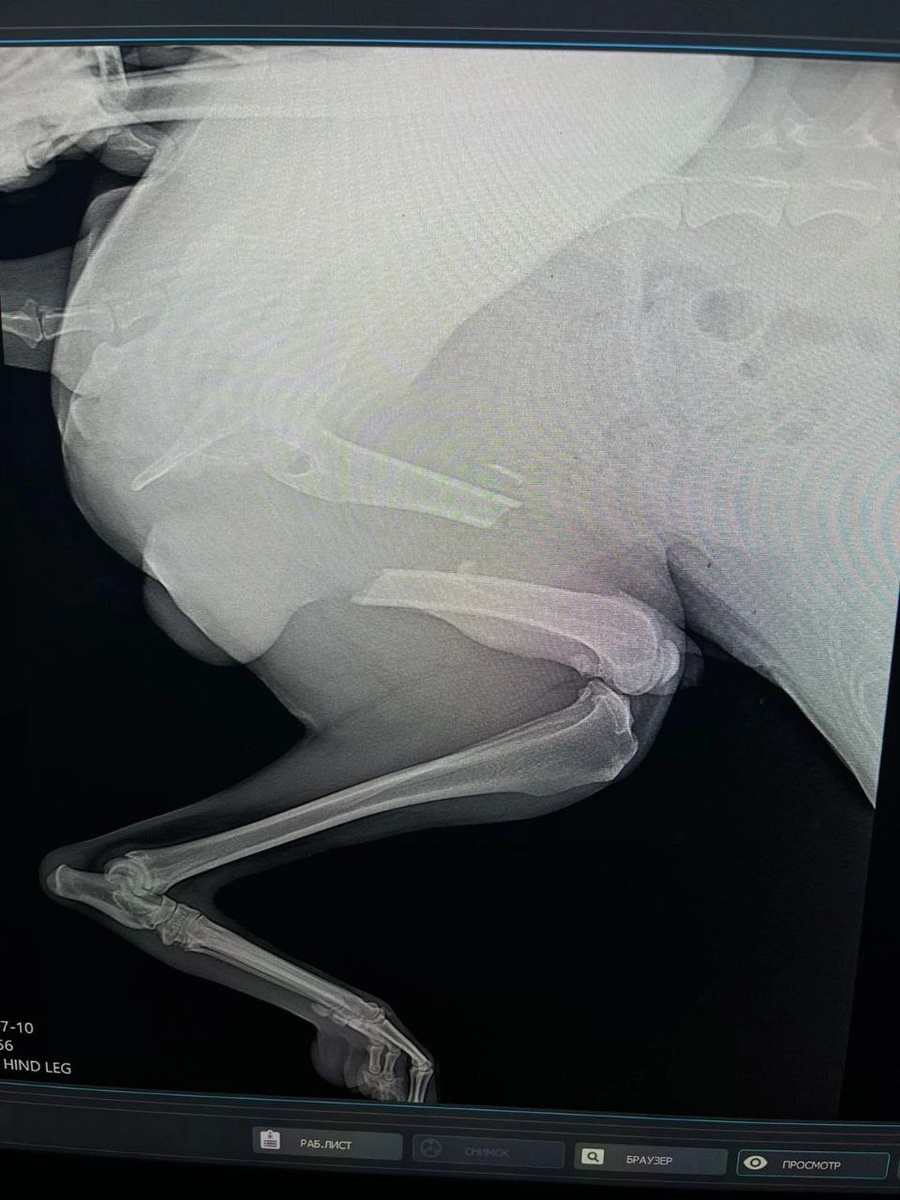

Неравнодушные орловчане оплатили дорогостоящее лечение бездомному псу! Информацию опубликовала группа помощи животным «Альфа». В селе Альшань появился пёс с перебитой лапой. Как оказалось, у животного был серьезный перелом. Оплатить процедуру вызвались местные жители, а это 15 000 рублей. К слову, собаке потребуется послеоперационная передержка, а ещё лучше – дом и любящие хозяева! Желающих помочь просят обращаться в группу «Альфа». Тем более, что в приюте есть и другие собаки. Возможно, кто-то найдет там себе настоящего четвероногого друга. (Фото: Приюта "Альфа") @1oblastnoi

В селе Альшань появился пёс с перебитой лапой. Как оказалось, у животного был серьезный перелом. Оплатить процедуру вызвались местные жители, а это 15 000 рублей.